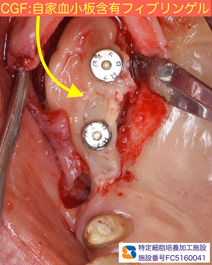

インプラント移植と骨の増殖を同時に行いました。

骨の増殖には、人工骨β-TCPとCGF(フィブリノーゲン)を混ぜた物を使用しています。

人工骨の変形や流出を避けるために、CGFメンブレンを利用しました。

これは、採血した自己血液を利用して、院内で製造したものです。

当院は、近畿厚生局が認可した再生医療加工施設です。